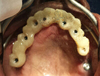

maxillaire pour recevoir les implants

Mise en place du bridge sur le maxillaire